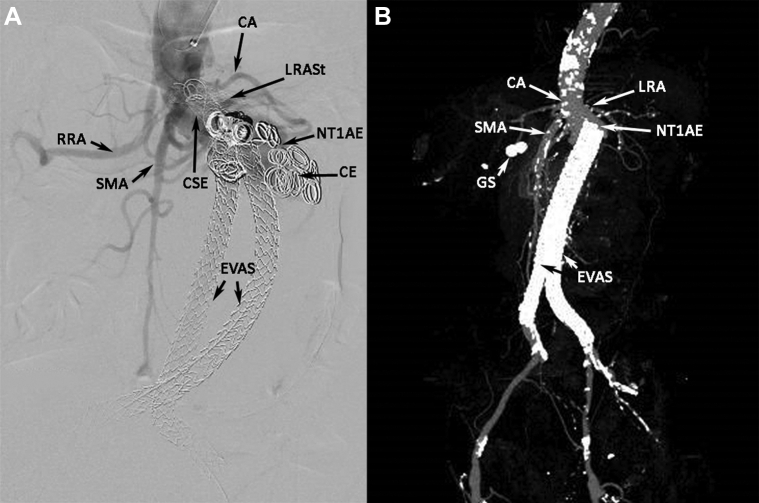

An 81-year-old man with a symptomatic, 8-cm-diameter, juxtarenal AAA and a 1.9-cm saccular right common iliac artery aneurysm underwent Nellix EVAS repair and treatment with a left renal artery (LRA) chimney covered stent. During polymer injection, the distal right common iliac artery ruptured and was treated successfully with a 10-mm × 59-mm BeGraft covered stent (Bentley Innomed, Hechingen, Germany). A computed tomography (CT) scan at the 14-month follow-up detected an NTIaE, an empty right endobag with caudal endograft migration, and interval occlusion of the left renal stent. An aortogram showed proximal covered stent extension of the right endograft plus coil embolization that was unsuccessful in obliterating the NTIaE (Fig 1, A).

Fig 1.

A, Aortogram showing Nellix type Ia endoleak (NTIaE) that was unsuccessfully treated with coil embolization (CE) and proximal covered stent extension (CSE). CA, Celiac artery, splenic artery branch; EVAS, endovascular aneurysm sealing with Nellix endografts; LRASt, left renal artery stent (occluded); RRA, right renal artery; SMA, superior mesenteric artery. B, Three-dimensional computed tomography aortogram (CTA) reconstruction showing new Nellix type Ia endoleak (NTIaE) with caudal migration of Nellix endografts (endovascular aneurysm sealing [EVAS]). CA, Celiac artery with severe ostial stenosis; GS, gall stones; LRA, left renal artery with proximal stenosis; SMA, superior mesenteric artery.

A 64-year-old man with severe cardiovascular comorbidities (ie, severe mitral regurgitation, ischemic heart disease, hypertension) underwent successful EVAS for a 5.2-cm-diameter AAA with a severe infrarenal neck angulation of 80°. He was well and followed up annually with CTAs for 2 years. He developed aortitis with presumed endograft infection without evidence of an endoleak at 30 months and was treated with intravenous antibiotics. At 32 months, the patient presented with pain. The CTA showed an NTIaE, an increased mycotic aneurysm size at the level of the RRA, and bilateral Nellix caudal migration (Fig 1, B).